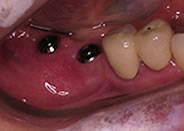

下顎の奥歯が1本ありません

レントゲンで欠損とその周囲の状態を調べます

埋入するインプラントを決定します

手術時間は30分程度でした

インプラントのX線像